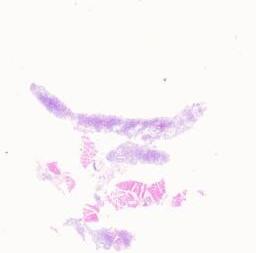

临床资料: 病人信息:患者,女,62岁,患者2月前无诱因间断发热,体温最高39.0℃,热型无规律,伴乏力、偶有咳嗽,无明显咳痰、胸痛、咯血、颈部疼痛、腹痛、腹泻、尿频、尿急、尿痛、关节肌肉疼痛、皮疹、双手雷诺、脱发、口腔溃疡等症,曾输液7天(具体不详),效不佳,发热时间断口服退热药,近1月诉持续发热。血常规:白细胞数目2.65×10^9/L;单核细胞百分比18.7%;淋巴细胞数目0.60×10^9/L;中性粒细胞数目1.53×10^9/L;嗜酸性细胞数目0.01×10^9/L;红细胞数目3.16×10^12/L;血红蛋白79g/L;红细胞压积25.8%;平均红细胞体积81.7fL;平均红细胞血红蛋白含量25.1pg;平均红细胞血红蛋白浓度306g/L;红细胞分布宽度变异系数17.3%;血小板压积0.296%;血沉134mm/h;C反应蛋白125.17mg/L;心肌酶谱(五项):乳酸脱氢酶361U/L;a羟基丁酸脱氢酶214U/L;降钙素原正常。EB病毒DNA定量(血清)(2025-11-1014:45:04):Eb病毒DNA定量2.216E+05IU/mL(参考范围:<1.00E+02IU/mL)。外周血形态分析:血红蛋白含量、红细胞数均减低。成熟红细胞大小不等,可见嗜多色红细胞。中性粒细胞核左移(杆状核粒细胞约占25%),可见少量中、晚幼粒细胞。部分中性粒细胞胞浆内可见粗大颗粒、空泡。血小板常见。骨髓细胞形态学:增生活跃骨髓象,粒系核左移,部分细胞可见毒性改变;内铁阳性率减低,请结合临床及其他检查。骨髓活检:倾向炎症性病变,请结合临床、感染及其他相关检查进一步协诊,原幼细胞比例小于5%,巨核细胞未见明显病态造血,未见明显异型淋巴细胞,浆细胞比例小于5%。查体:颈部、腋下、腹股沟等处多发淋巴结肿大。大体检查:灰红色结节一枚,大小为2.3×1.8×1cm,切面灰白色,质地细腻。(取材部位:右颈部淋巴结)